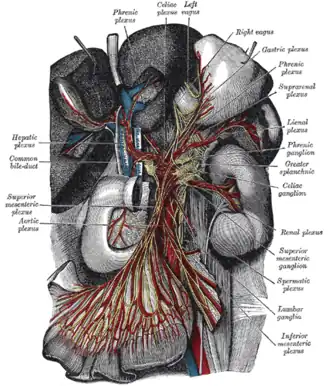

The celiac ganglia or coeliac ganglia are two large irregularly shaped masses of nerve tissue in the upper abdomen. Part of the sympathetic subdivision of the autonomic nervous system (ANS), the two celiac ganglia are the largest ganglia in the ANS, and they innervate most of the digestive tract.

They have the appearance of lymph glands and are placed on either side of the midline in front of the crura of the diaphragm, close to the adrenal glands. The ganglion on the right side is placed behind the inferior vena cava.

The upper part of each ganglion is joined by the greater splanchnic nerve, while the lower part, which is segmented off and named the aorticorenal ganglion, receives the lesser splanchnic nerve and gives off the greater part of the renal plexus.

Innervation

These ganglia contain neurons whose postganglionic axons innervate the distal esophagus, stomach, proximal duodenum, liver, gallbladder, spleen, kidney, and the small intestine. They directly innervate the ovarian theca and secondary interstitial cells and exert an indirect action on the luteal cells.

Abdominal portion of the sympathetic trunk, with the celiac and hypogastric plexuses.

Abdominal portion of the sympathetic trunk, with the celiac and hypogastric plexuses. -